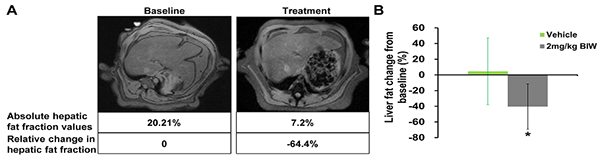

B1344对高脂饮食喂养的食蟹猴脂肪肝的治疗作用

符合入选标准的肥胖食蟹猴接受B1344治疗或对照处理,第69天通过磁共振成像(MRI)测定肝脏脂肪。(A)经每周两次给予2 mg/kg B1344治疗后的猴子肝脏脂肪含量的MRI测量结果;(B)经每周两次给予2 mg/kg B1344治疗后的猴子肝脏脂肪含量的定量测定结果。